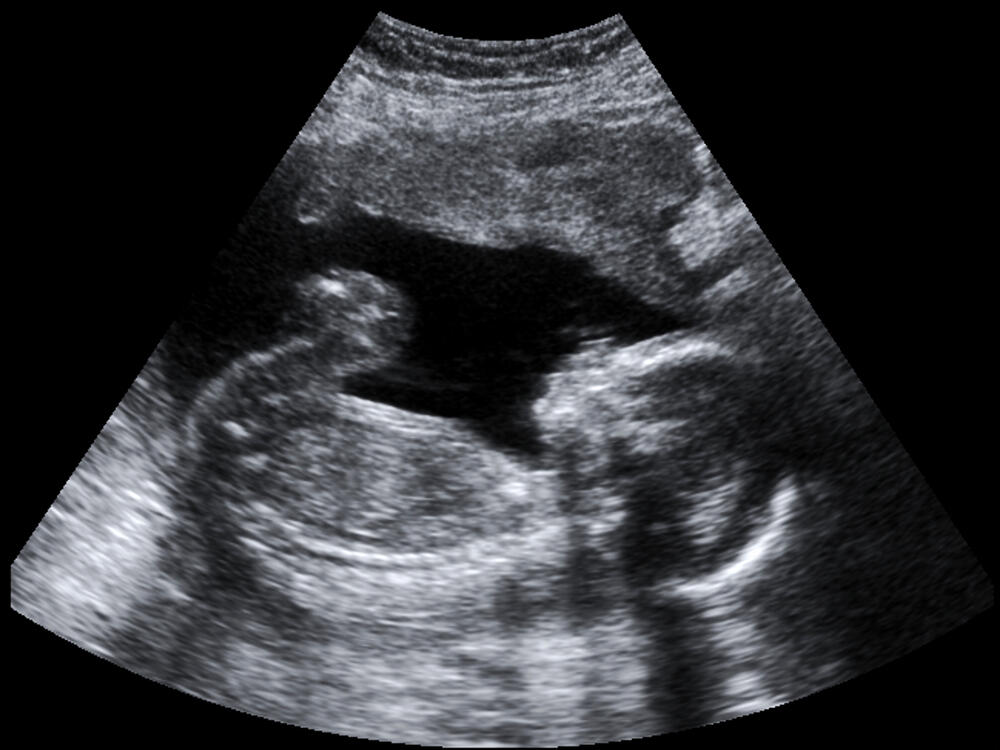

Od kog trenutka čovjek postaje čovjek? Njemačka administracija mrtvorođenčad koja su teška manje od 500 grama ne upisuju u matične knjige. Roditelji su se izborili za izmjenu tog zakona.

Barbara i Mario Martin su roditelji. Trostruki. Međutim, Jozef-Lenard i blizanci Tamino i Penelope nisu živi. Svo troje rođeno je prerano.

Prvog sina, Jozefa Lenarda, porodica Martin je izgubila u sedmom mjesecu trudnoće. Beba je imala 440 grama.

Poslije godinu dana bračni par je zadesila istovjetna sudbina. Barbara je nosila blizance i u sedmom mjesecu trudnoće je prerano rođeno mrtvorođenče Tamino. Imao je 290 grama.

Dugo se smatralo da novorođenčad koja teže manje od 500 grama nisu sposobna za preživljavanje. Međutim, zahvaljujući savremenoj medicini i bebe koje imaju 300 grama uspijevaju da prežive. Martinovi ipak nisu htjeli da se pomire sa činjenicom da u Njemačkoj zakon određuje da li je čovjek priznat ili ne. Sebi su zadali cilj da promijene zakon o ličnom statusu.